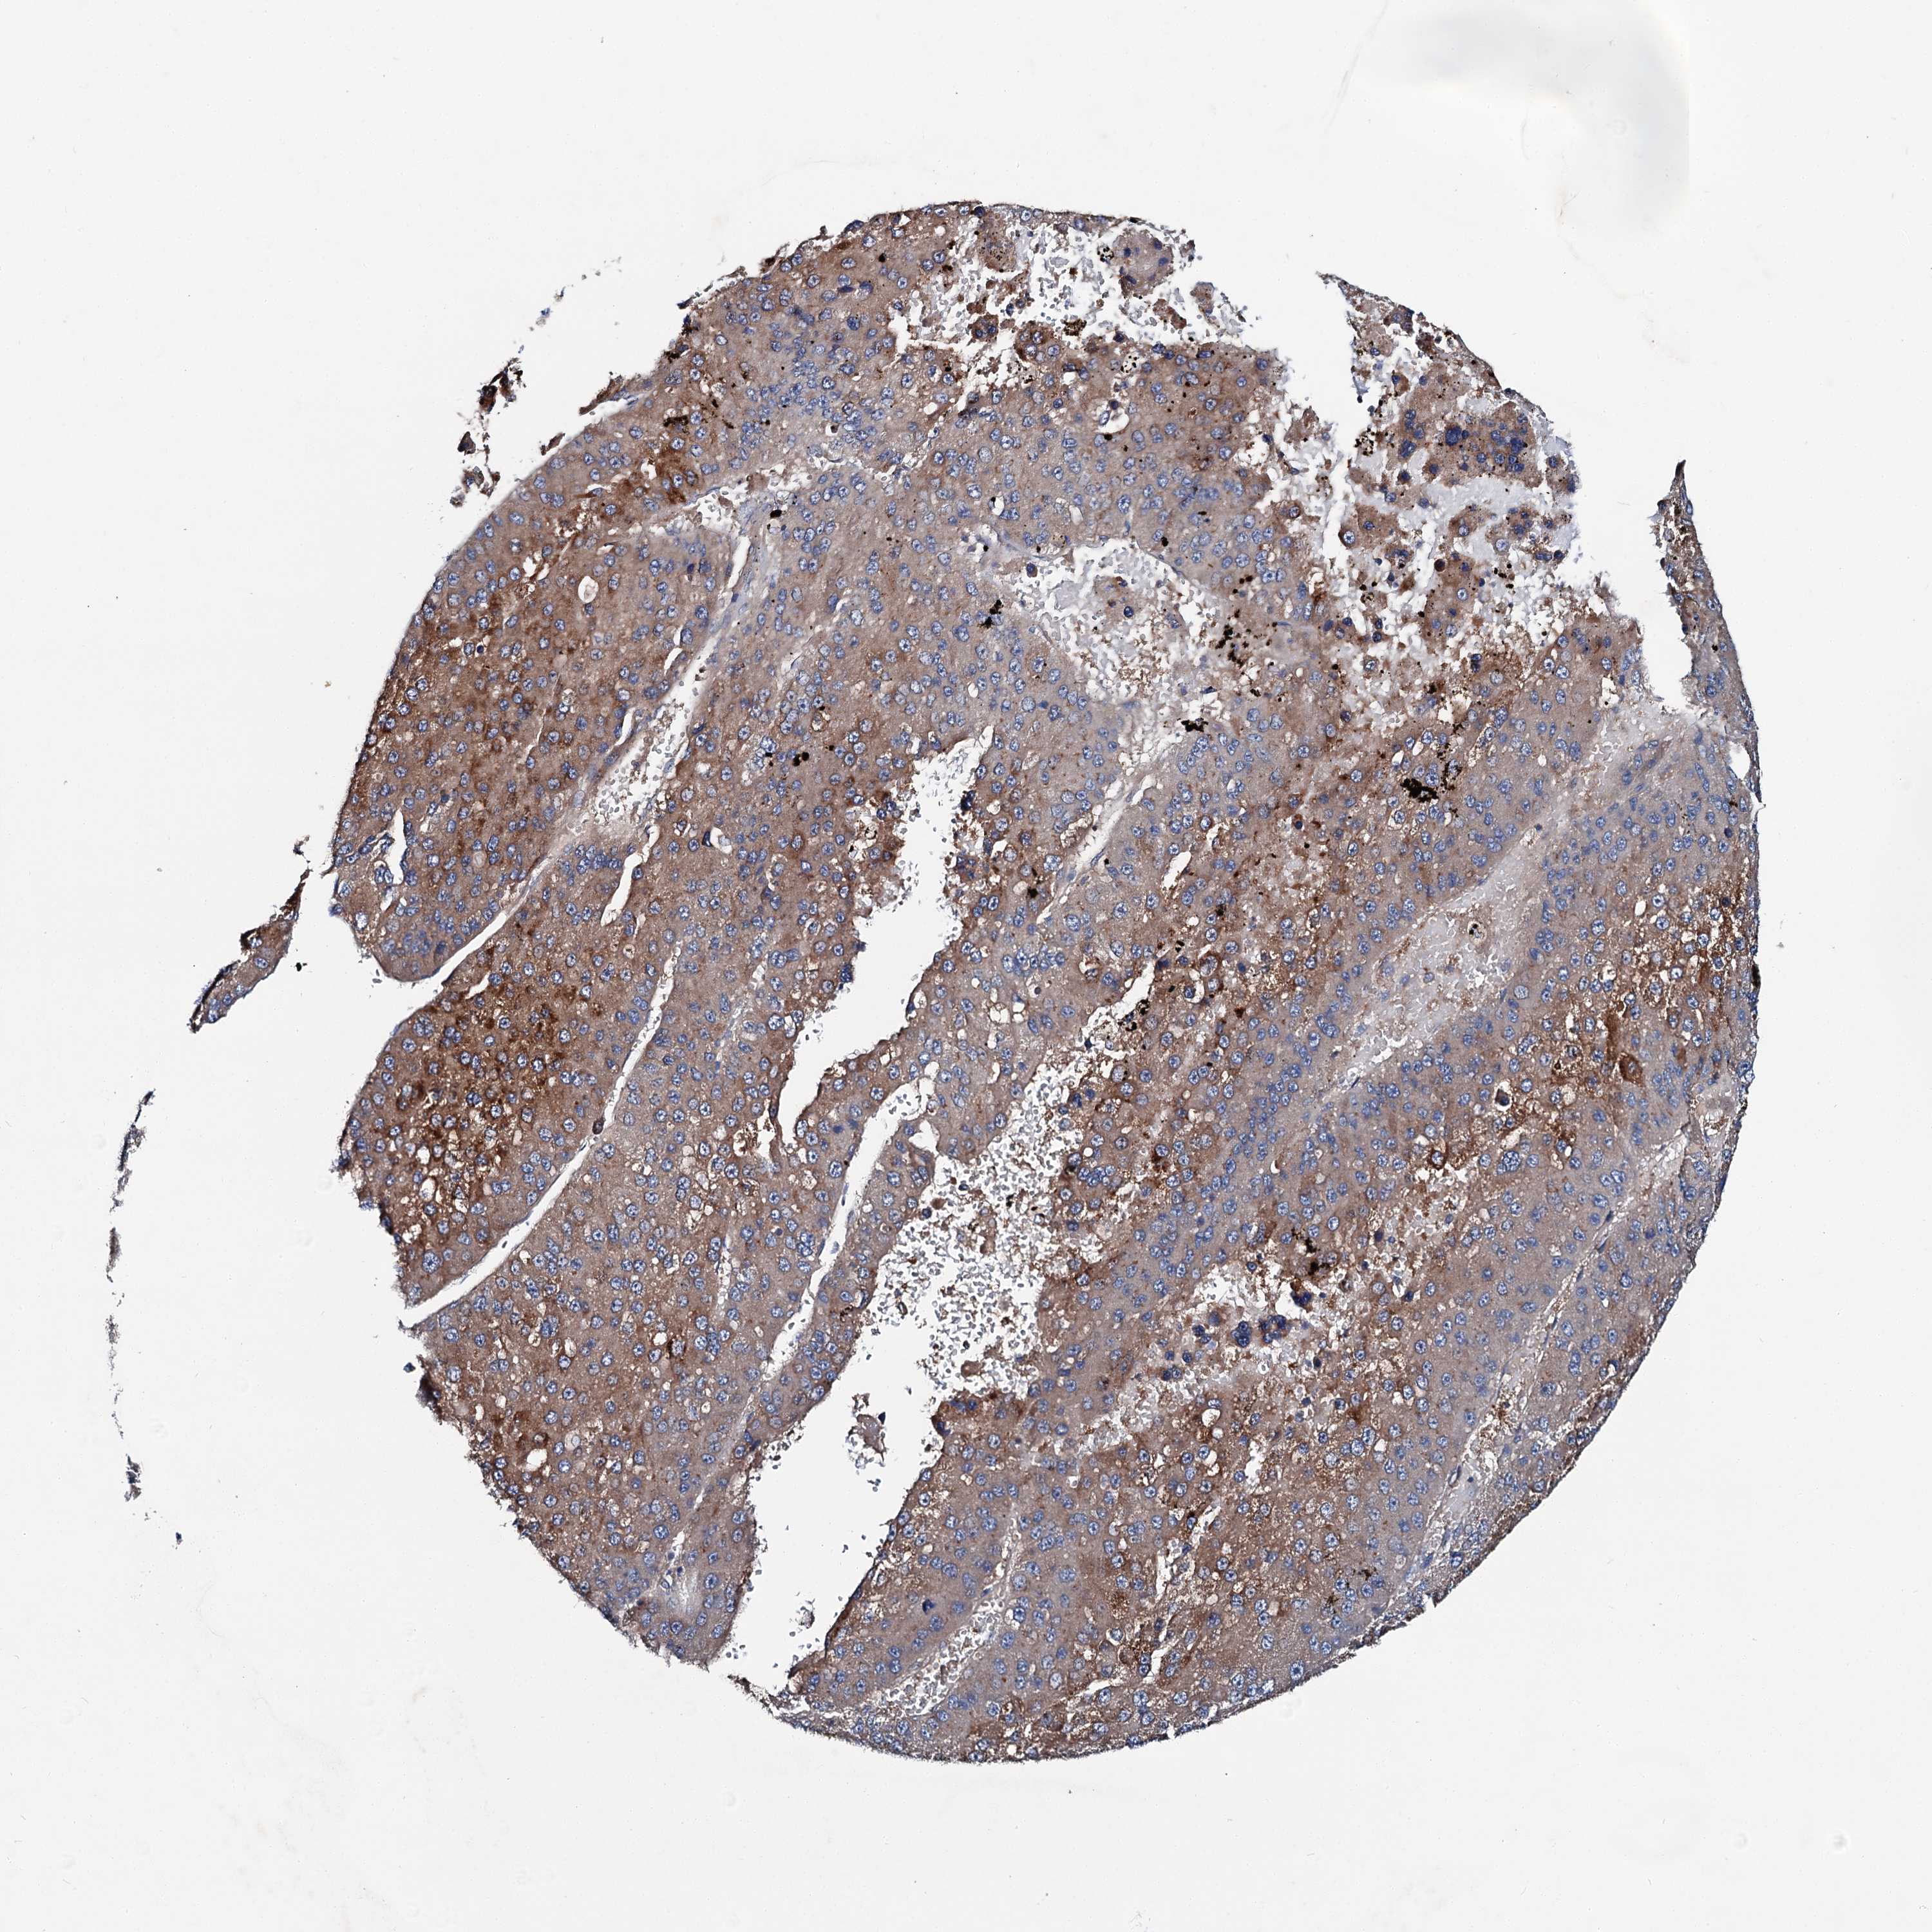

LIVER CANCER - Protein expressioni

A mouse-over function shows sample information and annotation data. Click on an image to view it in a full screen mode. Samples can be filtered based on level of antibody staining by selecting one or several of the following categories: high, medium, low and not detected. The assay and annotation is described here.

Note that samples used for immunohistochemistry by the Human Protein Atlas do not correspond to samples in the TCGA dataset.

Antibody stainingi

Antibody staining in the annotated cell types in the current human tissue is reported as not detected, low, medium, or high, based on conventional immunohistochemistry profiling in selected tissues. This score is based on the combination of the staining intensity and fraction of stained cells.

Each image is clickable and will lead to virtual microscopy that enables deeper exploration of all samples and also displays staining intensity scores, fraction scores and subcellular localization as well as patient and tissue information for each sample.

Antibody HPA039390

Staining

High

Intensity

Strong

Quantity

>75%

Location

Nuclear

Cholangiocarcinoma

Carcinoma, Hepatocellular, NOS